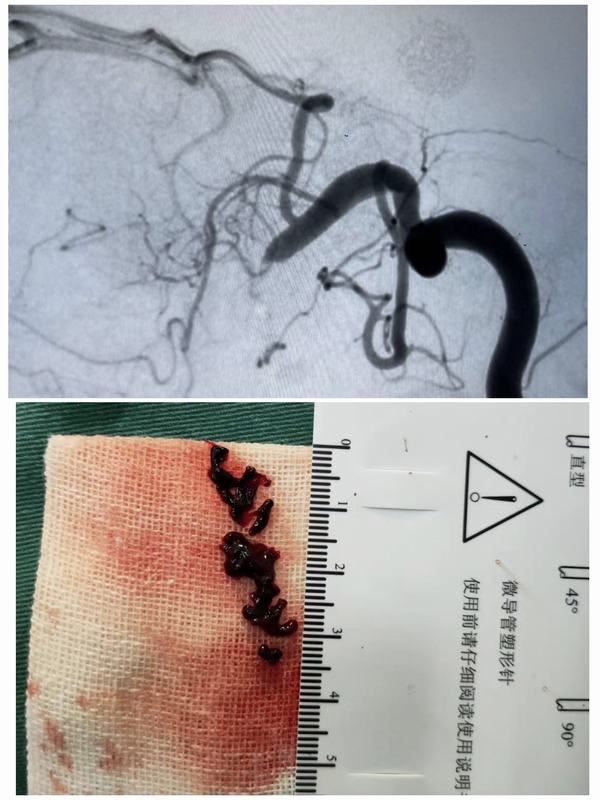

2月23日中午12:00,腦病急診科接診一名59歲女性患者,急性起病,主因:突發(fā)左側(cè)肢體無力1.6小時。經(jīng)查體患者神志清,精神差,言語不利,左側(cè)肢體肌力0級。立即開通綠色通道,急查頭顱CT示:右側(cè)基底節(jié)區(qū)及右側(cè)側(cè)腦室前角旁多發(fā)腔梗。家屬簽字同意后給予靜脈溶栓治療。12:20患者進入導(dǎo)管室行全腦血管造影+動脈溶栓術(shù)+機械取栓術(shù)。患者于3月3日出院,出院時患者神志清,精神狀態(tài)良好,左側(cè)肢體肌力正常、言語清晰,入院時癥狀得到完全緩解。

腦卒中具有高發(fā)病率、高致殘率、高死亡率、高復(fù)發(fā)率的特點,給社會、家庭帶來了沉重的負擔(dān),但只要4.5-6小時內(nèi)進行靜脈溶栓,必要時動脈取栓的積極治療,多可獲得更好的療效。